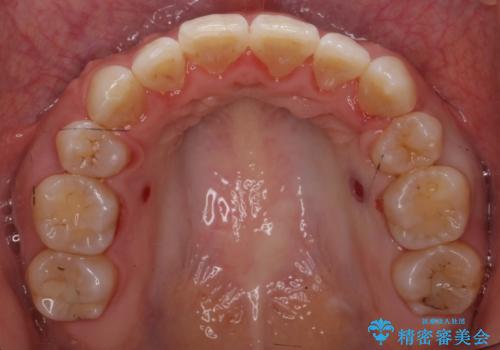

矯正治療で右下を抜歯し、スペースを天然の歯でつめる矯正治療を行いました。

治療期間はかかりましたが、右下4が一生もつとは思えない状態でしたので、人工物を入れないようにすることができました。

矯正治療をしない場合は、右下はブリッジかインプラントが必要になっていたと思います。

上顎前歯も唇側傾斜しておらず、もともと叢生が多くない状態で上下左右を抜歯した上、リンガルで治療を行なったため、多少治療期間がかかりました。